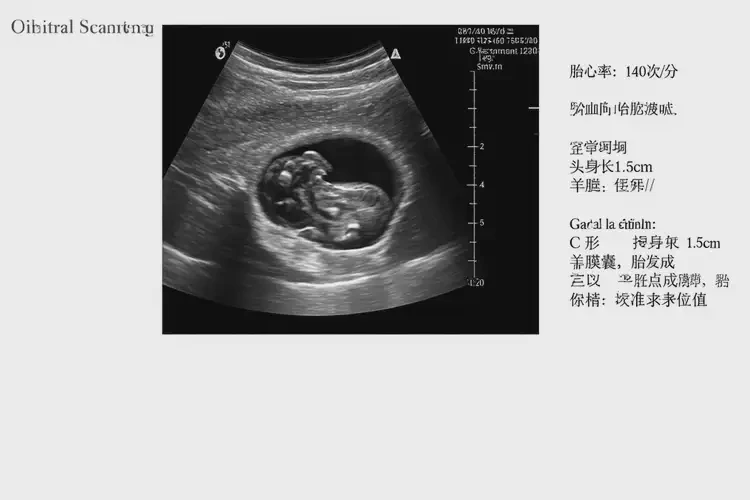

孕8周3天胎心97還要保胎嗎(圖1)